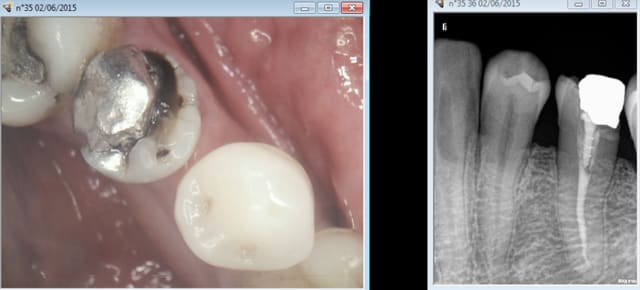

RTE ! -))) Et IC coiffes dans la foulée non mais ! On peut meme se payer le luxe d' etre pulpo conscient et résister à dégainer le R25 en faisant un petit compo offert dans la foulée ! ( 24)

Ca manque un peu d'illustration ce post ! Investissez dans une caméra bordel ! et montrez votre savoir faire-))))

Endo de merde rime avec SC 33 de merde, endo de qualité rime avec inlay core, ca vous étonne ? Dur dur de gagner sa vie avec des soins opposables en les faisant correctement, hein ?-))))

14 était fracturée initialement,, motif de la consult.

Chicot29 , tu utilises un bistouri electrique pour faire le méchoui de gencive ?

La prothèse c'est pas mon truc. Mais dans le temps imparti pour faire le tt de A à Z l'expérience montre qu'il faut en consacrer le plus pour l'endo. -))))